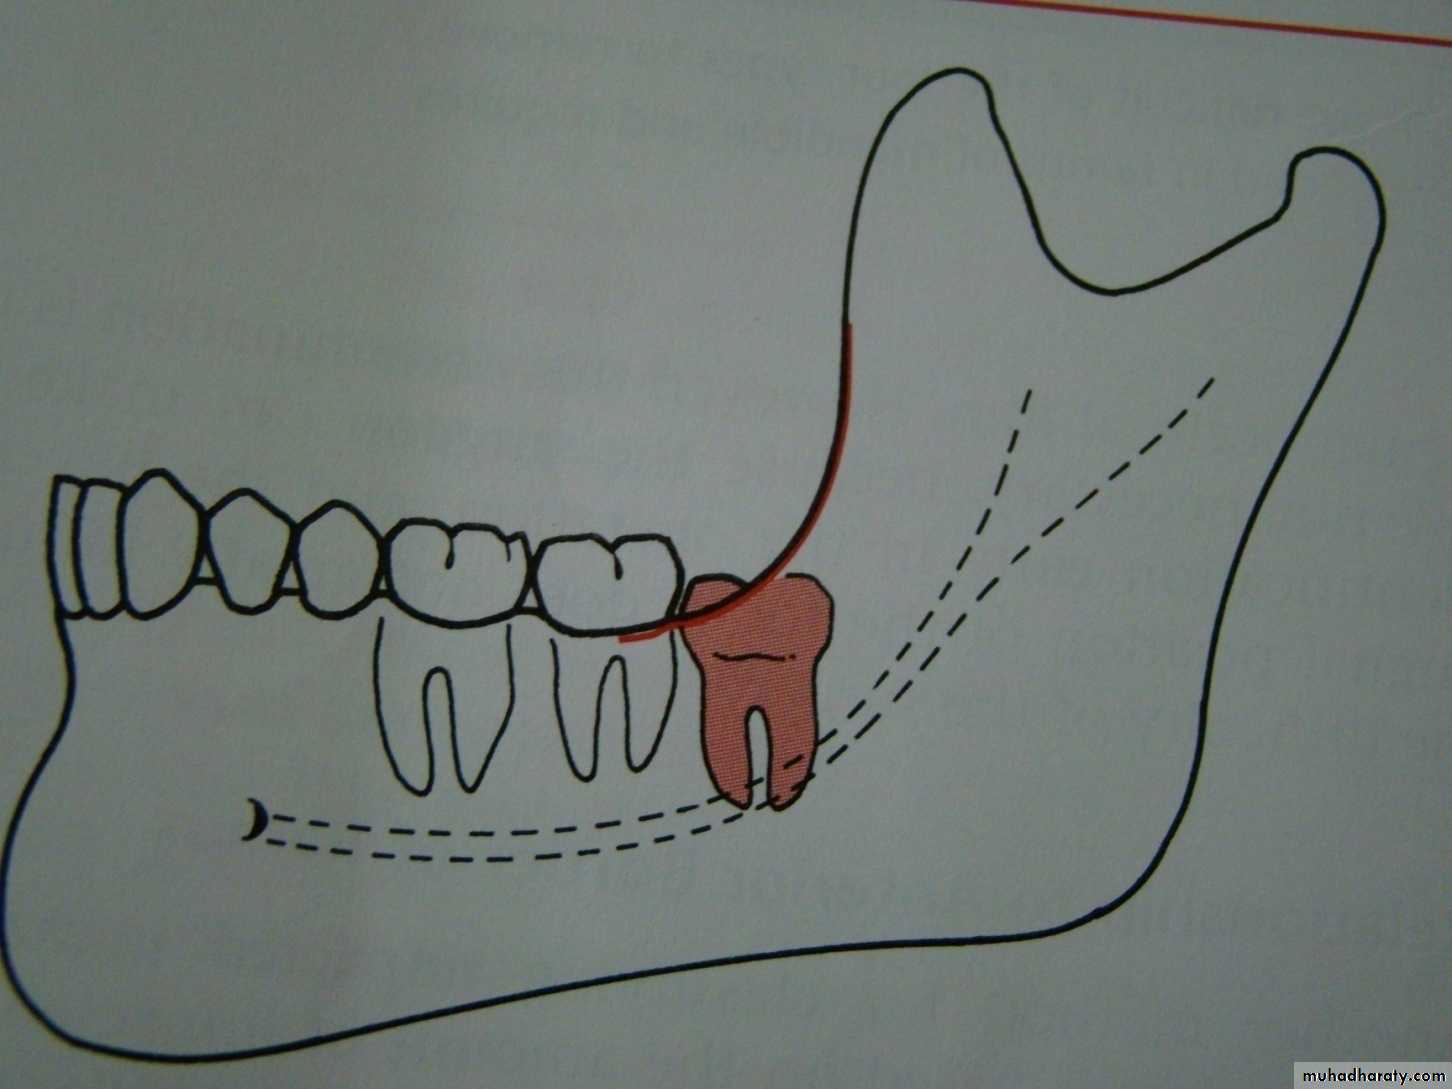

Winters classification of impacted lower third molarMesio angular

Disto angular

Horizontal

Vertical

Inverted

Transverse

Buccoversion

Linguversion